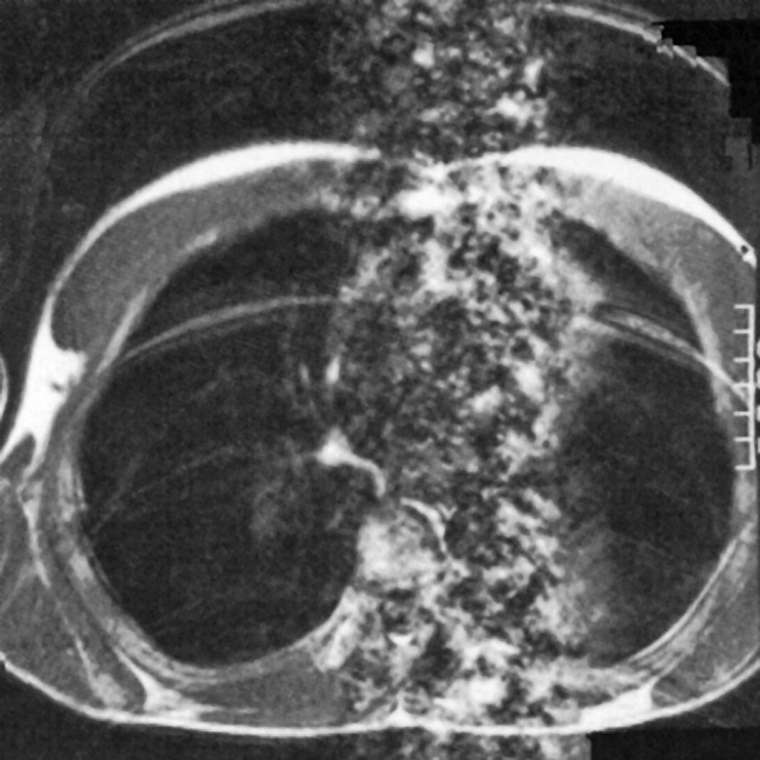

Figura 17-07:

Ghost images resulting from respiratory and cardiac motion with both sets of ar­ti­facts being oriented along the phase en­cod­ing gradient. The respiratory motion produces a number of distinct ghost ima­ges of the chest wall, while the cardiac mo­tion results in the column of noise as­so­cia­ted with the heart.